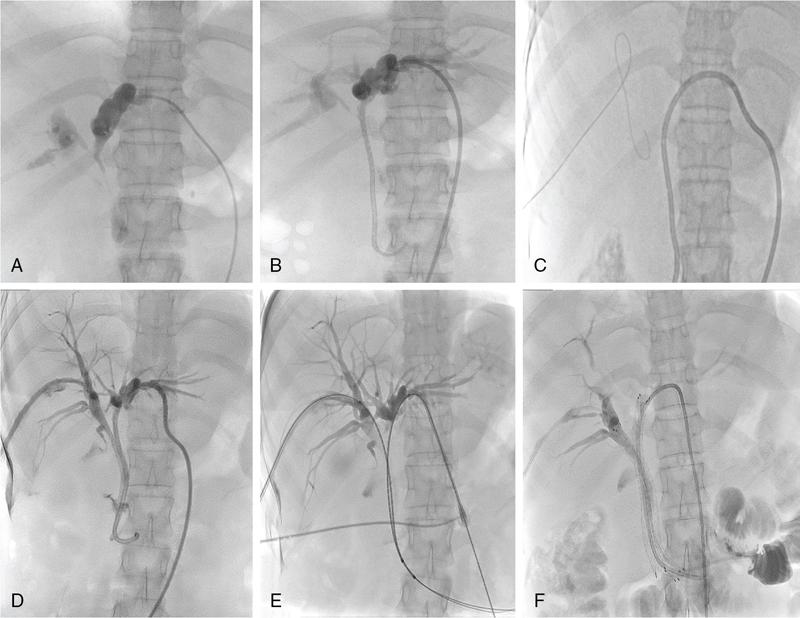

In patients with unresectable malignant biliary obstruction, biliary drainage provides palliation. External or combined internal–external drainage PTBD catheter is uncomfortable for the patient, requires constant care and causes psychological discomfort. Catheter-related complications such as pericatheter leak, tube blockage and kinking and dislodgement occur frequently and add to the morbidity of the patient. Placement of a stent for internal drainage overcomes these complications. Indications for metallic stents include malignant biliary obstruction, mostly in nonresectable cases. Uncommonly, retrievable stents are also placed for BBSs. Stents may be placed intrahepatically for tumours beyond hilum (unilateral or bilateral), in the bile duct and even as bowel stents where tumours invade the gastrointestinal tract beyond ductal entry. There are no absolute contraindications for biliary stenting. Relative contraindications are similar to that for PTBD. Preprocedure imaging is important to identify the type and location of the malignancy. This often helps to decide whether unilobar (Fig. 9.24.12) or bilobar stent (Fig. 9.24.13) is needed. It also helps to define the length of the stricture, although, length of the stent is based on cholangiographic measurements. Further, imaging is important to confirm that the disease is unresectable, as placement of stent makes surgery challenging in resectable cases. Patient preparation is similar to that for PTBD. The initial steps are same as for PTBD till the point of internalization. Then, either the stent is placed as a primary procedure or later as a secondary procedure. After placement of a stiff guidewire, the stent device is inserted over it. The ideal position of the stent is when its proximal and distal ends extend at least 1 cm and preferably 2 cm from the proximal and distal ends of the stricture, respectively. After stenting, an access catheter (5F) is usually placed in situ and the stent is evaluated with a cholangiogram after 48 hours. The metallic stent self-expands and allows internal biliary drainage with resultant decompression of the biliary system. The self-expanding metal stents are made of nitinol, and have thermal memory, allowing them to expand to their maximum diameter when they reach body temperature. This usually occurs in 24–48 hours. In cases, where the stent fails to expand adequately even after 48 hours, percutaneous balloon dilatation of the stent through the access catheter should be done for successful drainage. There are two broad categories of stents: plastic and metallic. Metallic stents can further be divided as covered and uncovered. Plastic stents are placed endoscopically and generally used for benign strictures. They have lower patency rates, require longer hospital stay and a higher overall cost, making them less suitable as palliative stents. Stent-related complications are being increasingly recognized due to the increased life expectancy of patients with stent insertions. This is attributed to the improved palliative care and management of these patients. The complications can be divided into early and delayed (Table 9.24.4).